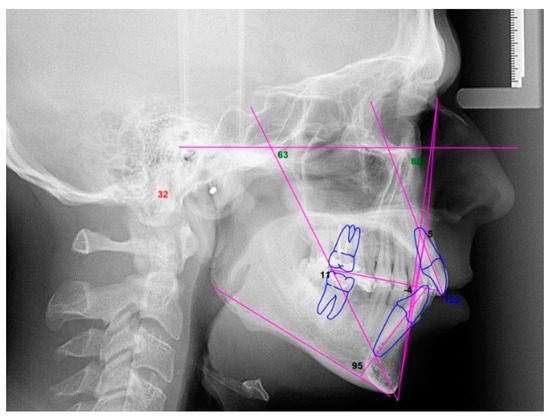

2.3.1. Example—Anterior Open-bite